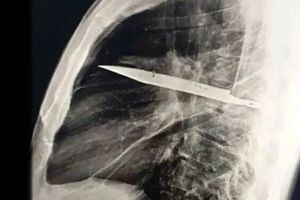

در یکی از نادرترین موارد پزشکی ثبتشده، مردی ۴۴ ساله اهل تانزانیا با ترشح چرک از قفسه سینهاش به اورژانس مراجعه کرد؛ اما آنچه پزشکان کشف کردند، فراتر از انتظار بود.